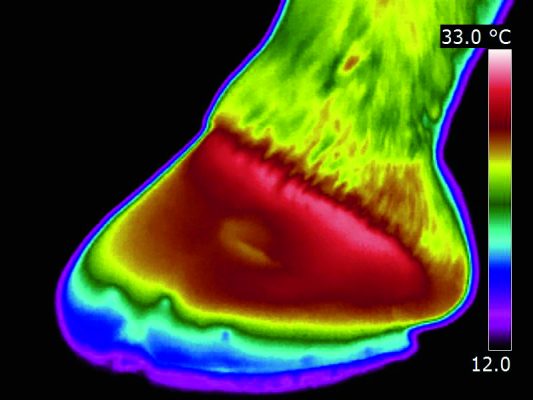

Veterinary Thermal Imaging hoof scan

Veterinary Thermal Imaging uses state of the art infra red cameras to map heat patterns across the horse’s hoof. The scan can assist with the detection and management of a range of issues, including laminitis, which can then be treated by a vet. This non-invasive service is completely mobile and doesn’t require the horse to be sedated.

RRP: £40 plus travel per pair of feet

Visit: www.veterinary-thermal-imaging.com or call 0844 544 3314